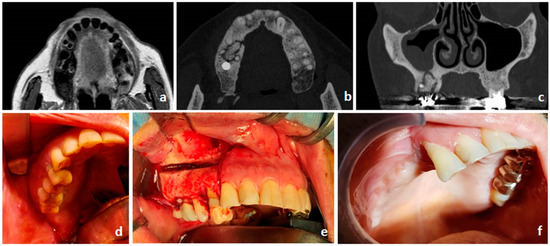

- Bedogni, A.; Blandamura, S.; Lokmic, Z.; Palumbo, C.; Ragazzo, M.; Ferrari, F.; Tregnaghi, A.; Pietrogrande, F.; Procopio, O.; Saia, G.; et al. Bisphosphonate-associated jawbone osteonecrosis: A correlation between imaging techniques and histopathology. Oral Surg. Oral Med. Oral Pathol. Oral Radiol. Endodontol. 2008, 105, 358–364. [Google Scholar] [CrossRef]

- Otto, S.; Baumann, S.; Ehrenfeld, M.; Pautke, C. Successful surgical management of osteonecrosis of the jaw due to RANK-ligand inhibitor treatment using fluorescence guided bone resection. J. Cranio-Maxillofacial Surg. 2013, 41, 694–698. [Google Scholar] [CrossRef] [PubMed]

- Bedogni, A.; Saia, G.; Bettini, G.; Tronchet, A.; Totola, A.; Bedogni, G.; Ferronato, G.; Nocini, P.F.; Blandamura, S. Long-term outcomes of surgical resection of the jaws in cancer patients with bisphosphonate-related osteonecrosis. Oral Oncol. 2011, 47, 420–424. [Google Scholar] [CrossRef]

- Otto, S.; Ristow, O.; Pache, C.; Troeltzsch, M.; Fliefel, R.; Ehrenfeld, M.; Pautke, C. Fluorescence-guided surgery for the treatment of medication-related osteonecrosis of the jaw: A prospective cohort study. J. Cranio-Maxillofacial Surg. 2016, 44, 1073–1080. [Google Scholar] [CrossRef] [PubMed]

- Stockmann, P.; Hinkmann, F.M.; Lell, M.M.; Fenner, M.; Vairaktaris, E.; Neukam, F.-W.; Nkenke, E. Panoramic radiograph, computed tomography or magnetic resonance imaging. Which imaging technique should be preferred in bisphosphonate-associated osteonecrosis of the jaw? A prospective clinical study. Clin. Oral Investig. 2010, 14, 311–317. [Google Scholar] [CrossRef] [PubMed]

- Bedogni, A.; Fedele, S.; Bedogni, G.; Scoletta, M.; Favia, G.; Colella, G.; Agrillo, A.; Bettini, G.; Di Fede, O.; Oteri, G.; et al. Staging of osteonecrosis of the jaw requires computed tomography for accurate definition of the extent of bony disease. Br. J. Oral Maxillofac. Surg. 2014, 52, 603–608. [Google Scholar] [CrossRef] [PubMed]